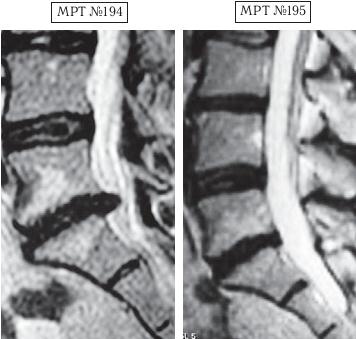

Напомню, что в большом спорте есть большая проблема — это допинги. Допинг в переводе с английского слова «doping» (от dope) означает «давать наркотики». По сути, это в основном химические препараты (фармакологические и другие средства), способствующие стимуляции физической и нервной деятельности на непродолжительное время. Иногда ими пытаются искусственно усилить физическую активность и выносливость спортсмена на время спортивных соревнований. В зависимости от специфики спортивной деятельности в качестве допинга могут использоваться, например, симпатомиметические амины (эфедрин, амфетамин, метиламфетамин и т. д.), стимуляторы центральной нервной системы и восстанавливающие, укрепляющие аналептики (трансамин, стрихнин, лептамин и т. д.), общестимулирующие средства (препараты лимонника китайского, женьшеня, левзеи и т. д.), этиловый алкоголь, наркотики, болеутоляющие средства (морфин, его производные, опиум) и другие препараты. Многие специалисты, не понаслышке знакомые с проблемами большого спорта, отмечают, что современный большой спорт — это уже не старый добрый спорт, где люди показывали свои физические достижения, а это уже во многом соревнование биохимиков по созданию лучшего допинга. Хотя с данной проблемой постоянно борется на международном уровне Всемирное антидопинговое агентство (ВАДА) — независимая организация, созданная при поддержке Международного олимпийского комитета (МОК), каждый год ужесточая антидопинговый контроль, однако всё равно каждый год фарминдустрия выдаёт новые «сюрпризы»-препараты. Печально то, что все эти химические допинги, которые тайно принимает спортсмен для одномоментного улучшения результата, неизменно отражаются на его здоровье, нанося ему ущерб. Ведь весь этот процесс носит экспериментальный характер, а это значит, что последствия для организма вполне могут стать необратимыми, а в некоторых случаях дело может закончиться и летальным исходом, что неоднократно случалось в практике большого спорта. Однако мало кто из спортсменов задумывается в момент приёма допинга о его отдалённых последствиях для своего организма. Многие спортсмены находятся в плену ошибочных стереотипов, которые гласят, что «если не будешь принимать допинг, не сможешь победить». Однако не зря говорится: «Познай себя и ты познаешь весь мир». Возможности человеческого организма многократно превышают возможности искусственной химии. Свидетельством тому является множество известных науке случаев, связанных как со спортом, так и с жизненными обстоятельствами, когда человек в экстремальных, чрезвычайных ситуациях способен проявить такие феноменальные способности и возможности, которые не всякий чемпион сможет повторить. Человеческий мозг — это далеко не изученная, сложная система центрального управления организмом, которая может функционировать в разных режимах, о чём неоднократно упоминается, например, в работах академика Натальи Петровны Бехтеревой. Так что не стоит искать обманчивых путей для достижения высот, ведь ничто не проходит в этой жизни бесследно. Как писал Омар Хайям: «Нищим дервишем ставши — достигнешь высот. Сердце в кровь разорвавши — достигнешь высот. Прочь, пустые мечты о великих свершеньях! Лишь с собой совладавши — достигнешь высот». Так что в любом деле важна внутренняя составляющая человека. Ради справедливости должен заметить, что среди моих пациентов, помимо спортсменов, немало просто самодисциплинированных людей, которые в полной мере ответственно, целеустремлённо подходят к вопросам своего здоровья. Это радует, поскольку понимаешь, что твой труд не пропадёт даром. Ведь если пациент столь тщательно будет следить и беречь своё здоровье и дальше, то организм ещё долго послужит ему верной службой. А это в свою очередь означает, что в жизни данного человека станет намного меньше проблем и он получит полноценную возможность для самореализации. Как говорится в пословице: «Жизнь дана на добрые дела». А тем читателям, кто на сегодняшний день обременён проблемой заболевания позвоночника, хочу сказать, что не стоит отчаиваться. Люди справлялись ещё и с худшими ситуациями. Доказательством тому служат как вышеизложенные, так и нижеприведённые случаи, которые даже высокопрофессиональным специалистам когда-то казались безнадёжными. Думаю, комментарии здесь излишни. Пример № 1. ![]() На МРТ № 192 наблюдается состояние поясничного отдела позвоночника: рецидив после операции — секвестрированная грыжа межпозвонкового диска в сегменте LIV-LV, абсолютный стеноз спинномозгового канала. На МРТ № 193 — состояние поясничного отдела позвоночника после лечения методом вертеброревитологии. Пример № 2. ![]() На МРТ № 194 наблюдается состояние поясничного отдела позвоночника после трёх операций: рецидив — грыжа межпозвонкового диска в сегменте LV-SI стеноз спинномозгового канала. На МРТ № 195 — состояние поясничного отдела позвоночника после лечения методом вертеброревитологии. Пример № 3. ![]() На МРТ № 196 наблюдается состояние поясничного отдела позвоночника после операций: рецидив грыжи межпозвонкового диска в сегменте LV—SI с формированием секвестра с миграцией в краниальном направлении, абсолютный стеноз спинномозгового канала. На МРТ №s197 — состояние поясничного отдела позвоночника после лечения методом вертеброревитологии. Пример № 4.